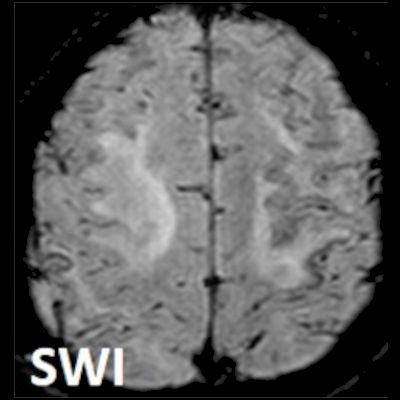

- Bilateral asimetrik subkortikal ve derin beyaz cevherde T1 ağırlıklı görüntülerde belirgin hipointens (oklar), T2A görüntülerde hiperintens (oklar), gri cevhere bakan kesimi düzgün (oklar), DAG’de hiperintens (ok) lezyonlar izlendi. Lezyonlarda T2/FLAIR uyumsuzluğu vardı (ok). Serebellar beyaz cevherde dentat nukleusu koruyan hilal işareti görüldü (ok başı). SWI sekansta sol motor kortekste hipointens kronik glioinflamatuar reaksiyon ile uyumlu sinyal değişikliği izlendi (ok başı).

- PML lezyonlarında kronik olarak aktive olan glial hücreler ve mikroglia/makrofajlar sitoplazmalarında yüksek seviyelerde demir ve pigment içerebilir ve SWI da hipointens olarak görülür.